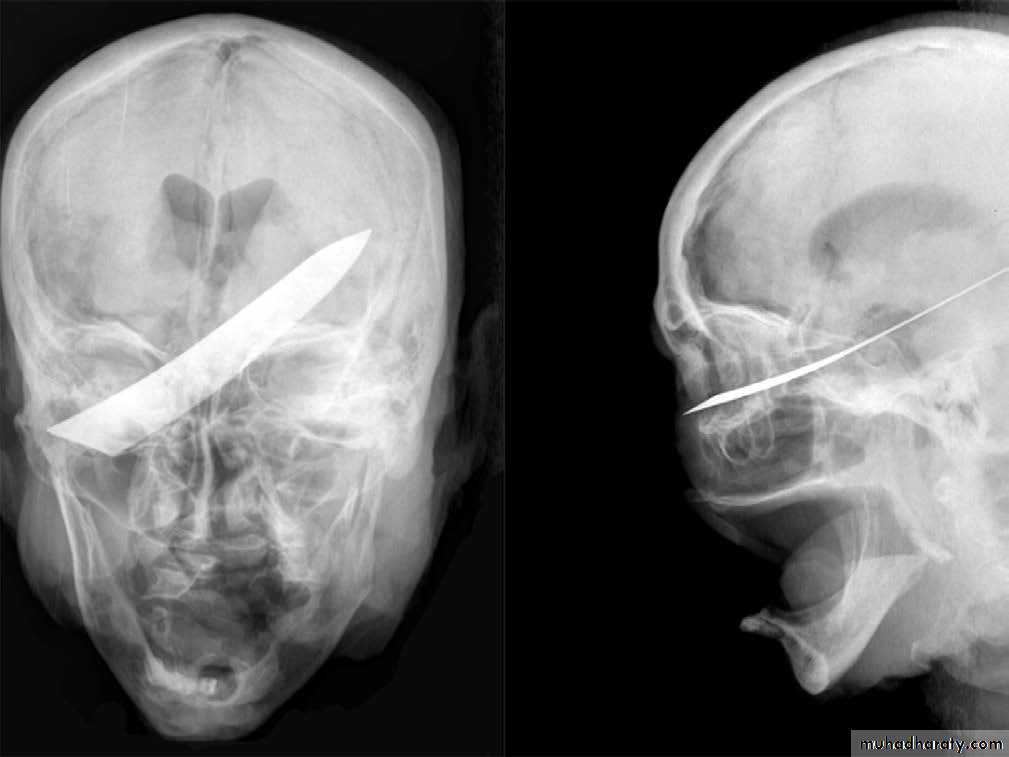

Broken blade of a kitchen knife protruding from the eye. The victim was stabbed to death and dismembered thereafter by the perpetrator

X-ray of the skull of the victim in previous case , showingthe position of the knife blade.